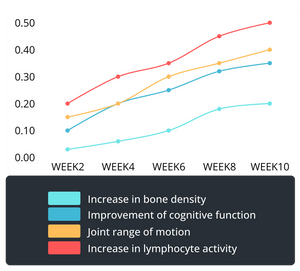

Red light stimulates mitochondria to boost adenosine triphosphate (ATP) production, providing essential energy for cell repair and regeneration. This accelerates recovery from muscle fatigue, enhances cellular renewal, and improves skin vitality.

Scientific Support: A 2019 PNAS study showed red light increases ATP production by 40%, supporting its role in energy metabolism, muscle recovery, and cellular repair.

Red light enhances nitric oxide (NO) release, improving oxygen delivery and waste removal through better circulation. It relieves diabetic circulation issues, varicose vein symptoms, and cold extremities, while aiding recovery in athletes.

Scientific Support: The Circulation Journal reported red light therapy increases local blood flow by 39%, improving oxygenation and overall tissue health.